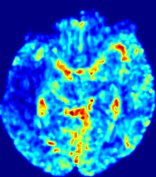

Slice #1Slice #2Slice #3Slice #4Slice #5Slice #6Dgtsuperscript𝐷gtD^{\text{gt}}Refer to captionRefer to captionRefer to captionRefer to captionRefer to captionRefer to caption(a)Refer to captionRefer to captionRefer to captionRefer to captionRefer to captionRefer to caption(b)Refer to captionRefer to captionRefer to captionRefer to captionRefer to captionRefer to caption(c)Refer to captionRefer to captionRefer to captionRefer to captionRefer to captionRefer to caption(d)Refer to captionRefer to captionRefer to captionRefer to captionRefer to captionRefer to caption(e)Refer to captionRefer to captionRefer to captionRefer to captionRefer to captionRefer to caption(f)Refer to captionRefer to captionRefer to captionRefer to captionRefer to captionRefer to captionRefer to caption000.060.060.060.120.120.120.180.180.180.240.240.240.300.300.30(mm2/s)𝑚superscript𝑚2𝑠(mm^{2}/s)

Figure 13: PIANO effectiveness and robustness testing: diffusion imaging via diffusion. Top row shows Dgtsuperscript𝐷gtD^{\text{gt}} used for simulating the ground truth pure diffusion. (a)-(f) refer to the results for D𝐷D estimated from the ground truth pure diffusion image time-series where Rician noise at levels 0%, 2%, 4%, 6%, 8%, 10% was added respectively.

Note this is likely not a spatially representative ground-truth for perfusion imaging, as it measures different effects from diffusion imaging. However, we still use it as a quasi-realistic pattern of diffusivity in the brain. We also added 2%, 4%, 6%, 8%, 10% levels of Rician noise to obtain simulations of ‘Diffusion Imaging’. The estimated Destsuperscript𝐷estD^{\text{est}} given concentrations of all noise levels for one patient are shown in Fig. 13, PIANO estimation results for all patients are summarized in Fig. 11 (b). Again, PIANO demonstrates its capability to recover the underlying diffusion field. In Fig. 13, when the noise level is increasing, some noisy patterns indeed appear in the associated Destsuperscript𝐷estD^{\text{est}}. Note that the ground truth diffusivity applied in this simulation experiment is about ten times larger than the diffusivity estimated in reality (Fig. 3, Fig. 4).